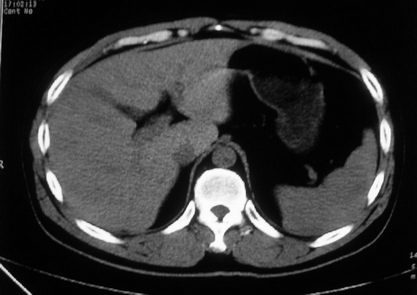

男,体查发现右肝低密度,右肾高密度结节影。高密度ct值92hu,囊肿?

肝右叶囊肿或血管瘤?右肾高密度囊肿。建议增强。

肝右叶圆形低密度灶,考虑囊肿或血管瘤,建议ct增强检查;右肾包膜下高密度圆形灶,考虑:囊肿并出血